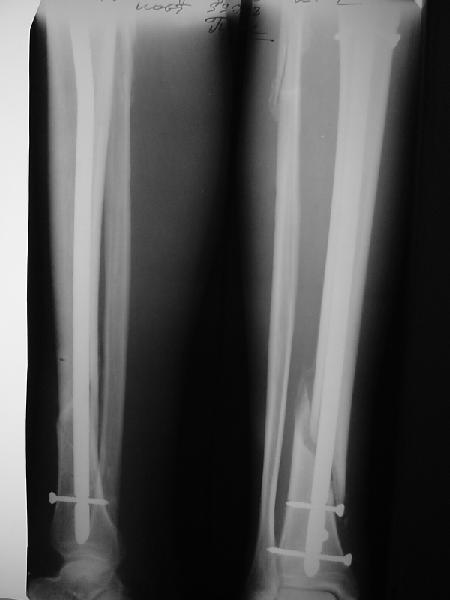

Это наглядная демонстрация возможности ранней полной нагрузки при нестабильном по оси повреждении, причем не в самых благоприятных механических условиях - при плохом сопоставлении, со слабым фиксатором.

Как я уже говорил, мы сделали выводы из этого и других подобных случаев. Очевидно, решений проблемы два - либо уменьшить нагрузку, либо увеличить прочность фиксатора. Первое решение работает не со всеми больными, так что пошли по второму пути - мы больше не используем гвозди с запирающими винтами диаметром 4 мм.